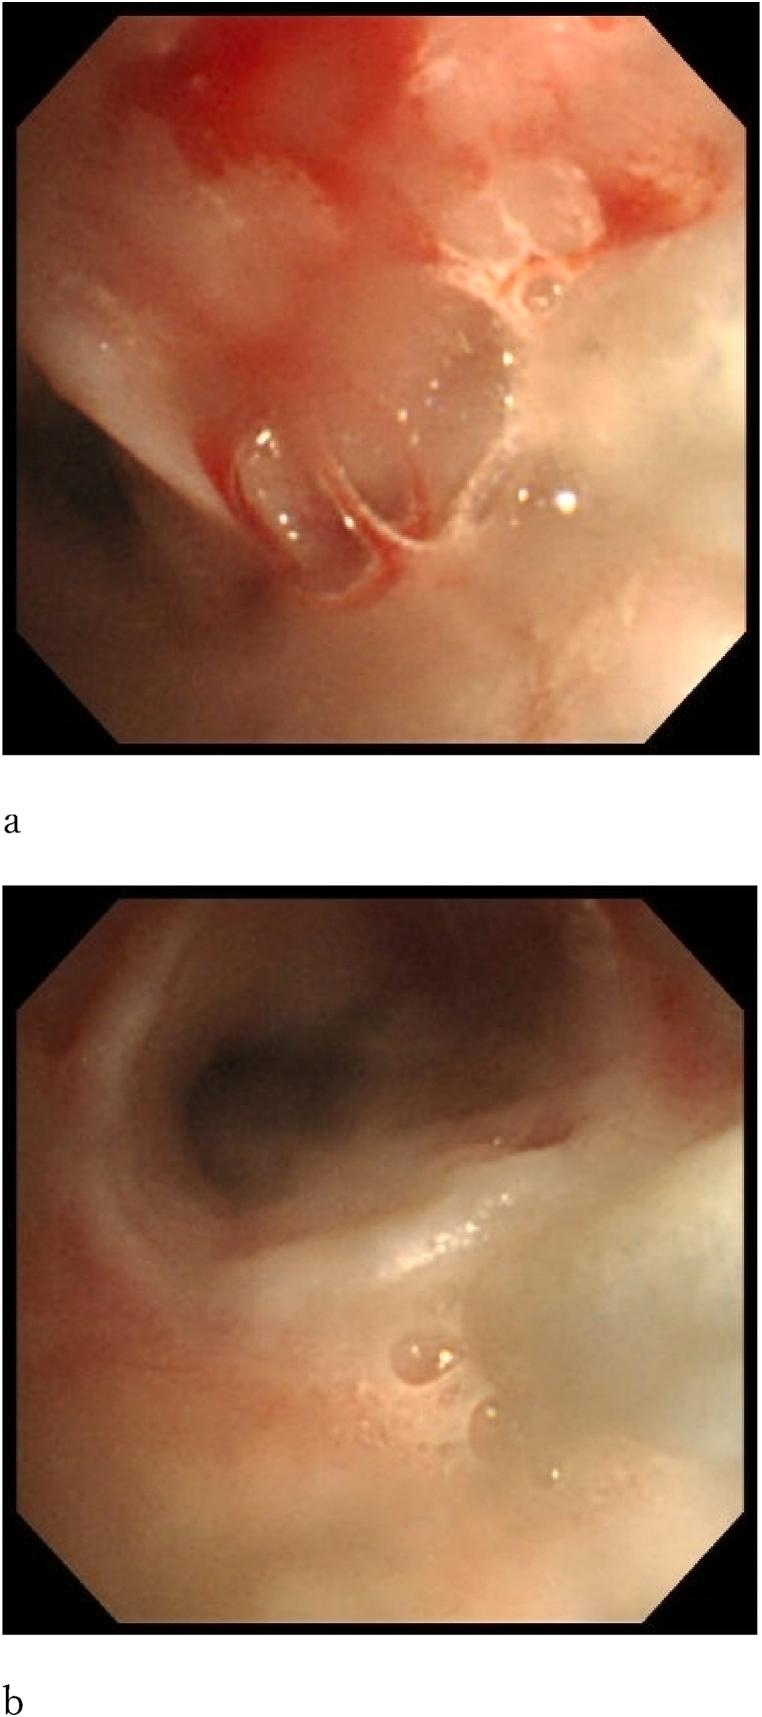

A 14-year-old boy presented to our pediatric department with epilepsy and psychomotor retardation. He was born at 24 weeks and 4 days of gestation and weighed 705 g at birth. He underwent a tracheostomy for tracheomalacia at 1 year of age. At the age of 12 years, granulation formed at the tip of the tracheostomy cannula, resulting in severe tracheal stenosis, which was repeatedly managed using ventilator management and replacement cannulas. As bronchoscopic cauterization and removal of the granulation tissue did not improve the condition, triamcinolone acetonide solution was injected into the granulation tissue three times, which resulted in regression of the granulation. Thereafter, no restenosis has been observed for more than 8 years.

一名14岁男孩因癫痫和精神运动发育迟缓就诊于我院儿科。他出生时孕周为24周4天,出生体重705克。1岁时因气管软化接受气管切开术。12岁时气管切开插管尖端形成肉芽组织,导致严重气管狭窄,多次采用呼吸机管理和更换插管进行处理。由于支气管镜烧灼和切除肉芽组织未能改善病情,遂向肉芽组织内注射曲安奈德溶液3次,肉芽组织消退。此后,8年多未观察到再狭窄。